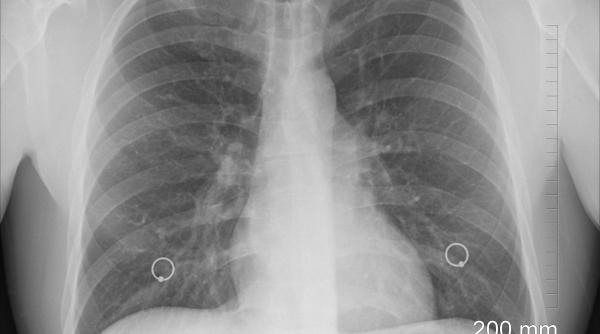

Publicat pe 09 Sep 2021 Cum arată tomografiile a patru pacienți nevaccinați, bolnavi de COVID. FOTO cu impact puternic: Nu vă jucați!